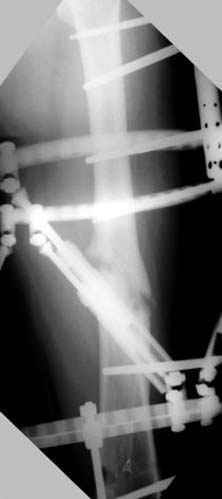

Отправитель: Djoldas Kuldjanov 23 Ноябрь 2004, 18:21

пластическая модель; и коррекция бедра аппаратом Илизарова.

Имею другие снимки тоже, получится как отчет о моей работе.

хотя даже если бы и инфекция , то nail exchange с рассверливанием канала - вариант дебрайдмента) Я думаю, что последовательность развития событий:

Узкий к-м канал - тонкий гвоздь- усталостный перелом дистальных винтов - развитие нестабильности и как ее результат остеолиз вокруг гвоздя - деформация анатомической оси бедра. Похоже, что я понял почему аппарат, а не новый гвоздь:-)